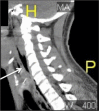

Pneumomediastinum Diagnosed on Ultrasound in the Emergency Department: A Case Report

A previously healthy patient was seen in the Emergency Department for evaluation of a one-month history of cough and one-day history of hemoptysis. This case report, from a pulmonologist's perspective, includes a comprehensive review of the patient's clinical presentation and outcome, as well as a discussion of recurrent respiratory papillomatosis.